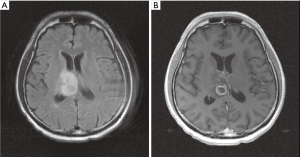

The patient then received a stereotactic brain biopsy. The diagnosis was CG. The tumor revealed epithelioid neoplastic cells with cord-like structures within a myxoid-rich stroma. The immunohistochemical (IHC) staining profiles showed positivity for GFAP, S-100 and CD34, negativity for EMA, with a Ki-67 index of 6.1% (Figure 2). The surgeon considered the tumor inoperable due to the location of the tumor. Local treatment by radiotherapy was suggested and accepted by the patient and family.

The characteristic of CG has its unique histologic and IHC features. Histologically, CG would resemble chordomas and chordoid meningiomas in its features of the clusters and cords of epithelioid cells within a mucinous vacuolated stroma (13). The IHC features included the positivity for GFAP, EMA, CD34, cytokeratin, S100 and vimentin. Lymphocyte infiltration was also commonly seen. The proliferative activity was generally low for CG. Mitoses were consistently low and no necrosis was ever reported (9,14-16). Desouza et al. have reviewed 50 cases of CG and indicated that the lymphocytic and plasma cell infiltrates were discussed in the ratio of 48 to 50 cases (96%). Likewise, the mucinous or myxoid stroma was discussed in the ratio of 49 to 50 cases. However, significant mitoses have only been found in 1 of the 45 cases so far. Ki-67 was recorded in 22 cases and ranged from 0.3% to 5% (17). Sanches et al. reported a unique case, a 59-year-old woman with a 2 cm CG, demonstrating GFAP and vimentin positivity, EMA negativity, and Ki-67 expression 20% (10). In our case, the tumor revealed epithelioid neoplastic cells with cord like structure in myxoid-rich stroma. The IHC stain showed positivity for GFAP, S-100 and CD34, and negativity for epithelial membrane antigen (EMA). Additionally, the Ki-67 index was 6.1% and it was slightly higher among other cases reviewed.